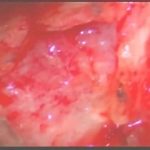

手術前2

摘出 中